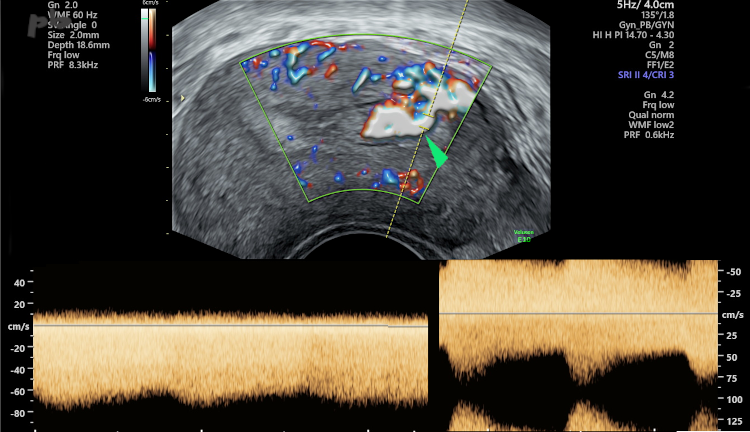

11 – Résidus trophoblastiques

Echographie doppler – Coupe transversale de l’utérus.

En doppler couleur, présence de flux nombreux et très rapides (►) au niveau de la corne gauche, atteignant 80 cm / s. Les résistances sont également très faibles.

2 tracés sont montrés, enregistrés à 2 endroits différents, avec les mêmes caractéristiques de haute vélocité et de résistances abaissées : flux de type utéro-placentaire. La vacuité a été obtenue spontanément, sans intervention.